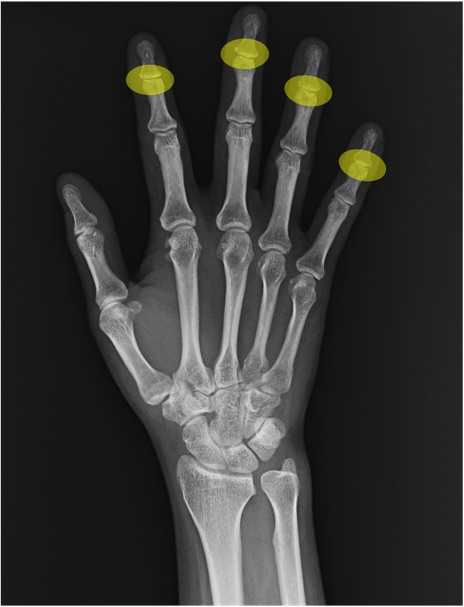

DIP関節(distal interphalangeal joint)の手関節レントゲン画像における正常解剖

舟状骨(scaphoid)

月状骨(lunate)

三角骨(triquetrum)

中手骨(metacarpal bone)

基節骨(proximal phalanx)

中節骨(middle phalanx)

末節骨(distal phalanx)

橈骨(radius)

尺骨(ulna)

尺骨茎状突起(ulnar styloid process)

CM関節(carpometacarpal joint)

IP関節(interphalangeal joint)

MP関節(metacarpophalangeal joint)

PIP関節(proximal interphalangeal joint)